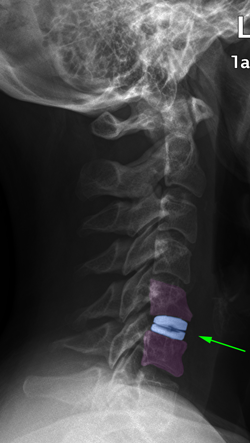

Αυχενικές δισκεκτομές με αρθροπλαστική (αριστερά), σπονδυλοδεσία με κλωβό (μέσο), σπονδυλοδεσία με κλωβούς πλάκα και βίδες. |